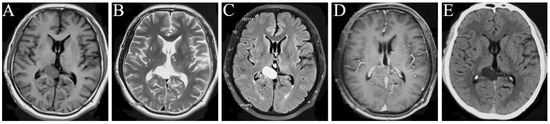

Figure 4.

MRI manifestations in follow-up two years after surgery on 1 August 2022. T1WI (A), T2WI (B), T2 Flair (C), and contrast-enhanced T1 (D) show the postoperative changes, and no occurrence was observed.

After 12 days of postoperative treatment, the patient recovered without complications and was discharged. No recurrence was observed in his last clinical follow-up on 1 August 2022 (Figure 4A–D).